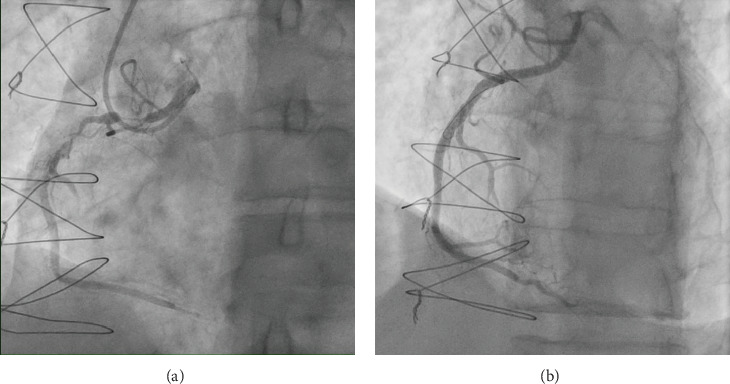

A 67-year-old male presented with non-ST elevation myocardial infarction (NSTEMI) with underlying anomalous origin of the right coronary artery (RCA) and a malignant course between the aorta and pulmonary artery. Previous CABG with LIMA and RIMA grafts had failed, leaving the patient with severe in-stent restenosis (ISR) in the LAD and degenerated, blocked grafts. The patient underwent percutaneous coronary intervention (PCI) to the anomalous RCA, which posed challenges in engagement due to its anomalous course. This case report discusses the complexities of managing such anatomies, emphasizing the role of CT coronary angiography, the difficulty of engaging anomalous arteries, and the techniques used to achieve successful PCI.